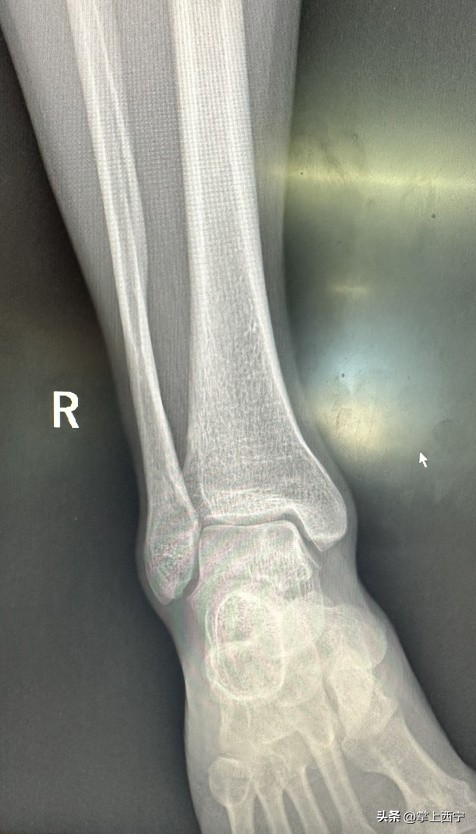

↑ 术前X射线平片

经过骨二科鲍义章主任和医师团队的进一步诊察,诊断为距骨软骨损伤并收治入院。患者入院后,医护人员为患者进行了充分的术前检查,经科室医师团队进行周密的病例讨论后,完善了各项术前准备,为患者施行了自体骨软骨移植术治疗距骨软骨损伤。